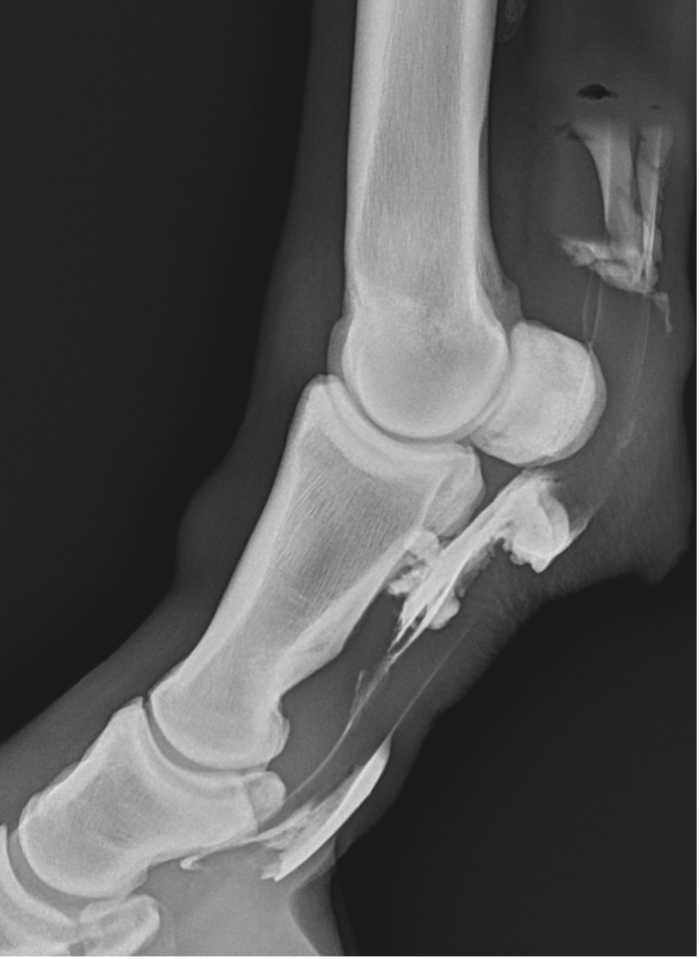

A Star Performer: 12-Year-Old Showjumping Crossbred Gelding

In this case report we look at a 12-year-old crossbred gelding who show jumps competitively to 1.40m.

Recently, the gelding developed acute tenosynovitis of the left hind digital flexor tendon sheath (DFTS) following a competition. Despite the owner’s efforts, which included icing, wrapping, and confinement for seven days, there was no improvement in the effusion of the DFTS.